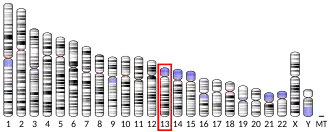

Gene

The 5-HT2A receptors is coded by the HTR2A gene. In humans the gene is located on chromosome 13. The gene has previously been called just HTR2 until the description of two related genes HTR2B and HTR2C. Several interesting polymorphisms have been identified for HTR2A: A-1438G (rs6311), C102T (rs6313), and His452Tyr (rs6314). Many more polymorphisms exist for the gene. A 2006 paper listed 255.[15][16]